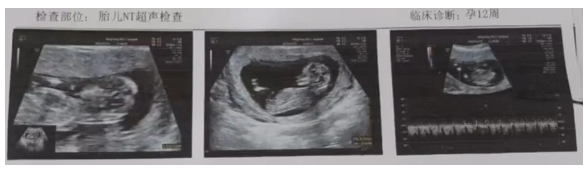

第一个周期促排后未妊娠。第二个周期继续促排,有成熟卵泡,2025年1月19日肌肉注射绒促素6000IU,于2月4日查血HCG449IU/L,2月8日阴道彩超见宫腔内囊样回声。2月13日阴道彩超见妊娠囊,内见极小的胎芽。3月30日NT检查通过,孕期顺利。

杨女士成功怀孕,胎儿发育良好,夫妻俩很开心,对李桂香医生连连道谢。